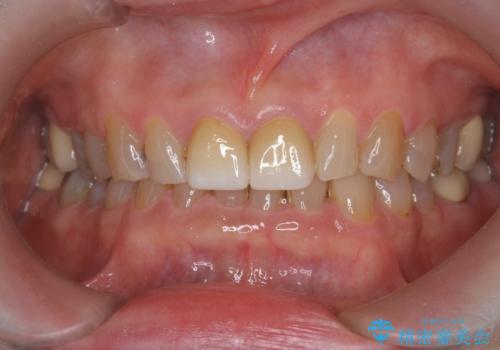

フルジルコニアクラウン治療について

フルジルコニアクラウンは全てジルコニアで生成されたセラミッククラウンで、前歯の噛み合わせが強い場合に切端の欠けを防ぎます。